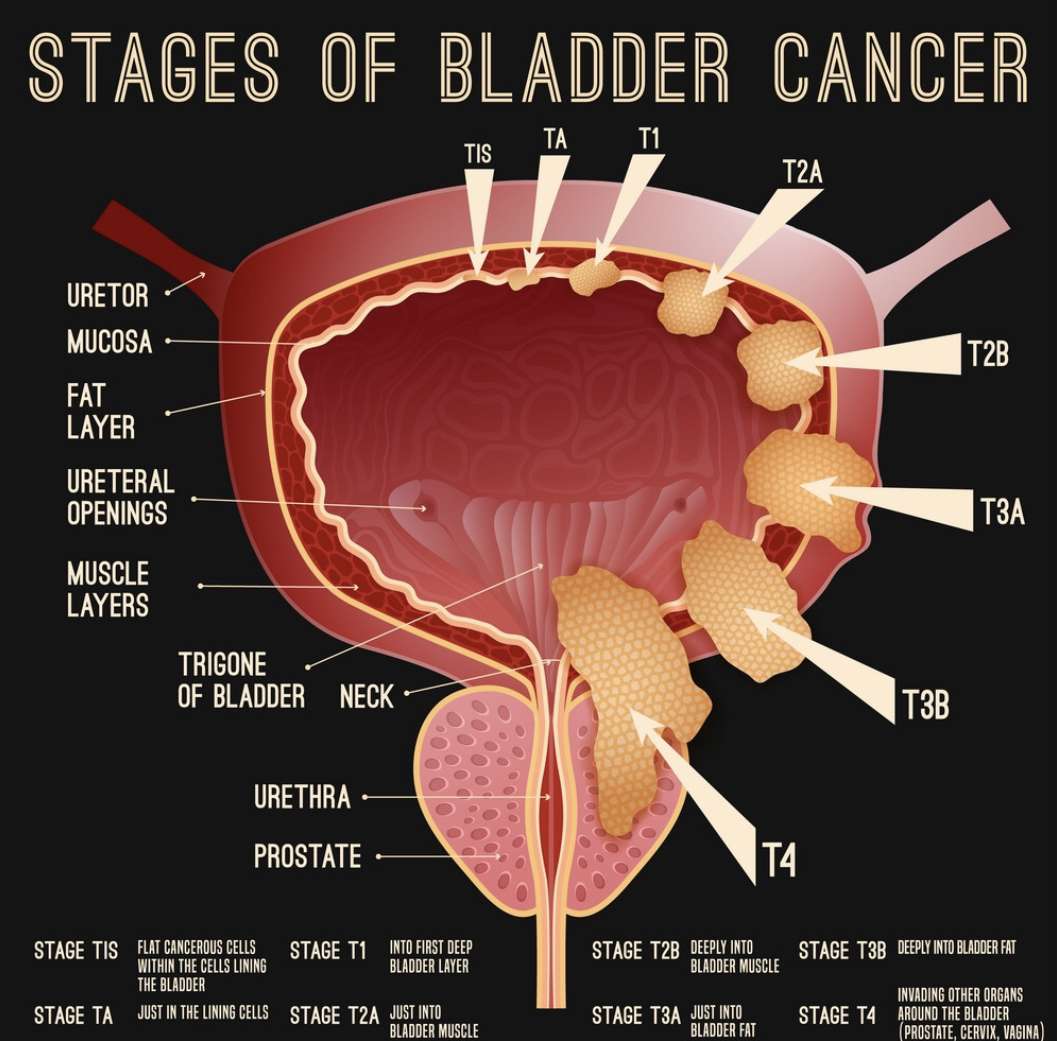

Illustration of different pathological stages of bladder cancer. Stage …

Bladder Cancer Stages And Grades – HealthyBladderClub.com

Staging and grading of bladder cancer – Macmillan Cancer Support

Classification Of Bladder Tumors : TNM stage classification of bladder …

Stages of bladder cancer from Meyer et al., (2002). Bladder cancer can …

Overview of staging and grading of bladder cancer tumor. The figure was …

Bladder cancer stages stock illustration. Illustration of inside – 10332948

Classification Of Bladder Tumors : TNM stage classification of bladder …

Bladder Cancer Staging | MedicineBTG.com